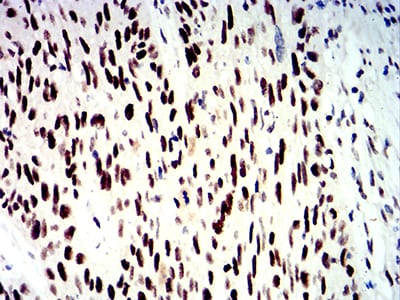

分类: 科研抗体货号: 31223别名: CIRP应用: IHC反应种属: Human